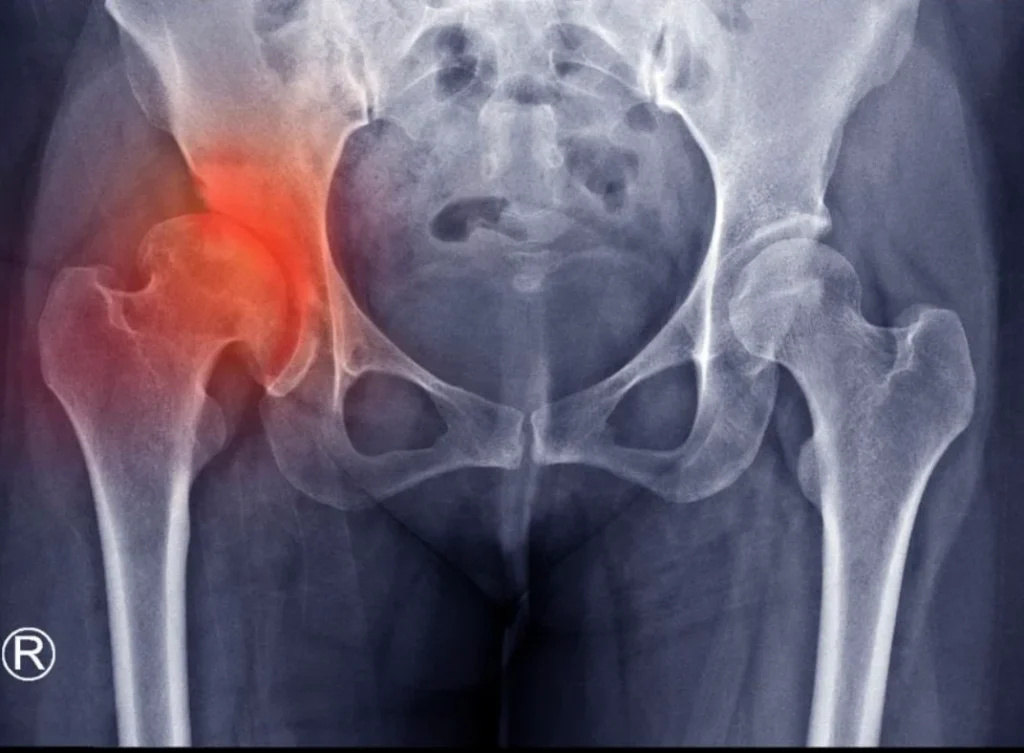

Στο κέντρο της άρθρωσης του ισχίου υπάρχει ένα στρώμα λείου χόνδρου που προστατεύει και απορροφά τους κραδασμούς καθώς τα οστά κινούνται. Όταν αυτός ο χόνδρος αρχίζει να λεπταίνει ή να φθείρεται, τα οστά τρίβονται μεταξύ τους, προκαλώντας πόνο, δυσκαμψία, φλεγμονή και τελικά μια κατάσταση γνωστή ως οστεοαρθρίτιδα του ισχίου (ή αλλιώς κοξάρθρωση).

Η οστεοαρθρίτιδα του ισχίου (κοξάρθρωση) είναι συχνή πάθηση που επηρεάζει πολλές ηλικιακές ομάδες, όχι μόνο τους ηλικιωμένους. Οι αιτίες που αναφέρονται (γενετική προδιάθεση, υπερβολικό βάρος, επαναλαμβανόμενες κινήσεις, τραυματισμοί) είναι σωστές και επιβεβαιωμένες από την ιατρική έρευνα.

Επίσης, τα συμπτώματα που περιγράφονται (πόνος, δυσκαμψία, αδυναμία, τριξίματα, πόνος τη νύχτα κλπ.) είναι χαρακτηριστικά της οστεοαρθρίτιδας του ισχίου και η αντιμετώπιση που προτείνεται (ήπια άσκηση, φυσικοθεραπεία, απώλεια βάρους, φαρμακευτική αγωγή, χειρουργική επέμβαση) αποτελεί τον επιστημονικά τεκμηριωμένο τρόπο διαχείρισης της πάθησης.